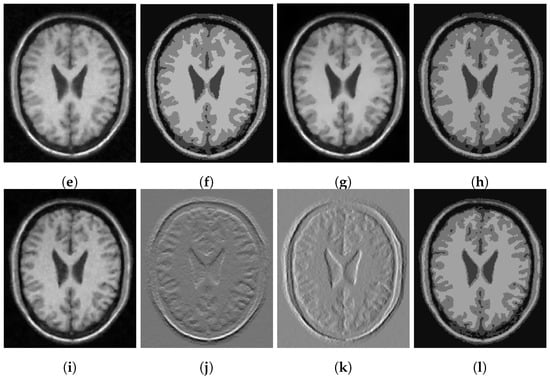

In Figure 3, Figure 4 and Figure 5, we show some examples of multiphase segmentation on MRI images of the brain. In all cases, we add Gaussian noise with mean 0 and standard deviation 17 and run the noisy image as input to both for all models but the CRCV model (as this is a two-phase model only). The output is then given as input to the k-means algorithm with . We show the clustering output in the final column of the relevant figures. We see that the segmentation result of our model is better at finding some of the finer edges; for example, the white matter segmentation from our model is in general more detailed than the segmentation from the competing ones.

Figure 5.

MRI segmentation: (a) Clean image. (b) Noisy image used as input to the models. (c) Output of CCZ. (d) CCZ after thresholding. (e) Output of CNC. (f) CNC after thresholding. (g) Output of T-ROF. (h) T-ROF after thresholding. (i) Output g of our model. (j) Output of our model. (k) Output of our model. (l) Ours after thresholding.